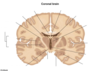

Anterior Pons Infarction

Anterior Pons Infarction